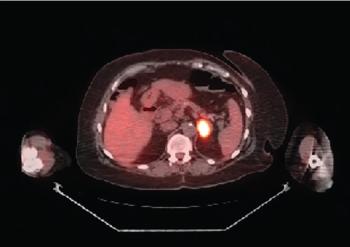

Recurrent EGFR-Mutated Non–Small Cell Lung Cancer Discovered by Abnormal Mammogram: Adjuvant/Frontline Metastatic Management Options

ByMehmet Sitki Copur, MD,Rudy P. Lackner, MD,Adam J. Horn, MD,Thomas Zusag, MD,Shellie Faris, MD,Paul Rodriguez, MD ABSTRACT:

Breast metastasis from extramammary malignancy is rare, with a reported incidence rate of 0.4% to 1.3% in the published literature. The primary malignancies that most commonly metastasize to the breast are leukemia, lymphoma, and malignant melanoma. Here, we report a very rare case of metastatic EGFR-mutated non–small cell lung cancer (NSCLC) in the breast detected by screening mammography. The patient had initially been diagnosed with a clinical stage IIIA NSCLC and had been treated with neoadjuvant chemoradiation followed by curative-intent surgery. Several interesting aspects of the case, along with a discussion of evolving adjuvant and frontline metastatic management options in EGFR-mutated NSCLC, will be presented.